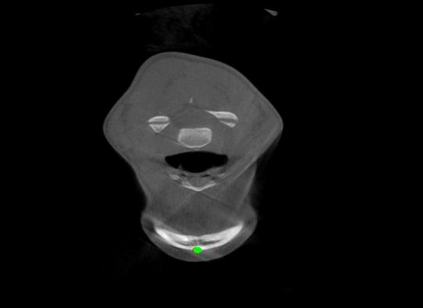

Detecting 3D landmarks on cone-beam computed tomography (CBCT) is crucial to assessing and quantifying the anatomical abnormalities in 3D cephalometric analysis. However, the current methods are time-consuming and suffer from large biases in landmark localization, leading to unreliable diagnosis results. In this work, we propose a novel Structure-Aware Long Short-Term Memory framework (SA-LSTM) for efficient and accurate 3D landmark detection. To reduce the computational burden, SA-LSTM is designed in two stages. It first locates the coarse landmarks via heatmap regression on a down-sampled CBCT volume and then progressively refines landmarks by attentive offset regression using multi-resolution cropped patches. To boost accuracy, SA-LSTM captures global-local dependence among the cropping patches via self-attention. Specifically, a novel graph attention module implicitly encodes the landmark's global structure to rationalize the predicted position. Moreover, a novel attention-gated module recursively filters irrelevant local features and maintains high-confident local predictions for aggregating the final result. Experiments conducted on an in-house dataset and a public dataset show that our method outperforms state-of-the-art methods, achieving 1.64 mm and 2.37 mm average errors, respectively. Furthermore, our method is very efficient, taking only 0.5 seconds for inferring the whole CBCT volume of resolution 768$\times$768$\times$576.